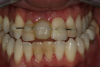

Case 2. Smile Zone Implant: Single Maxillary Central Incisor

Providing single-tooth restorations in the smile zone can be challenging; considerations for implant dentistry for a single maxillary incisor can be even more challenging. For this case, the digital workflow considerations were not much different from the previous case; radiographs, photography, and analog impressions were used. The patient was given alternative treatment options. He chose a single implant and final zirconia with cutback for porcelain application. The patient was advised about his surrounding vintage dentistry and told he should consider all maxillary anterior teeth, Nos. 6 through 11, be planned for better function and esthetics. The patient had the final say, which allowed the laboratory and the author to finalize the treatment plan with the definitive restoration.

Properly planning this case with digital dental technology offered a large quantity and quality of diagnostic information. Using the dental laboratory software to merge the entire 3D data set helped to predict the best outcome after the digital proposals for the implant abutment and final crown. The patient had been involved with implant dentistry and understood the value of technology available.

Figure 6 and Figure 7 depict a mature smile with many implant restorations. An analog impression was sent to the laboratory. The impression was scanned by the laboratory, a model was created virtually, and the implant dimensions and position were defined. The 3D surgical guide was fabricated (Figure 8), allowing the patient to receive his therapy swiftly and predictably. Tooth No. 8 was extracted, and the implant was placed and immediately loaded with an acrylic provisional treatment crown (Figure 9). The screw-retained treatment crown was fabricated in-office from a previously completed diagnostic wax-up.

Fig 6. Image of the patient’s mature smile.

Figure 6